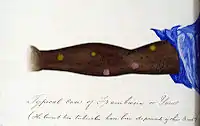

Within 9–90 days (but usually about 21 days[2]) of infection, a painless but distinctive "mother yaw" nodule appears.[2] Initially reddened and inflamed,[13] it may become a papilloma, which can then become an ulcer,[7] possibly with a yellow crust.[14] Mother yaws are most commonly found on the legs and ankles, and are rarely found on the genitals (unlike syphilis)[2] The mother yaw enlarges and becomes warty in appearance. Nearby "daughter yaws" may also appear simultaneously. This primary stage resolves completely, with scarring, within 3–6 months.[13] The scar is often pigmented.[2]

Papilloma mother yaw

Papilloma mother yaw.jpg.webp) Mother yaw nodule with central ulceration and a yellow crust

Mother yaw nodule with central ulceration and a yellow crust Ulcerated mother yaw

Ulcerated mother yaw Ulcerated mother yaw

Ulcerated mother yaw Healed primary yaw lesion, showing pigmented scar

Healed primary yaw lesion, showing pigmented scar